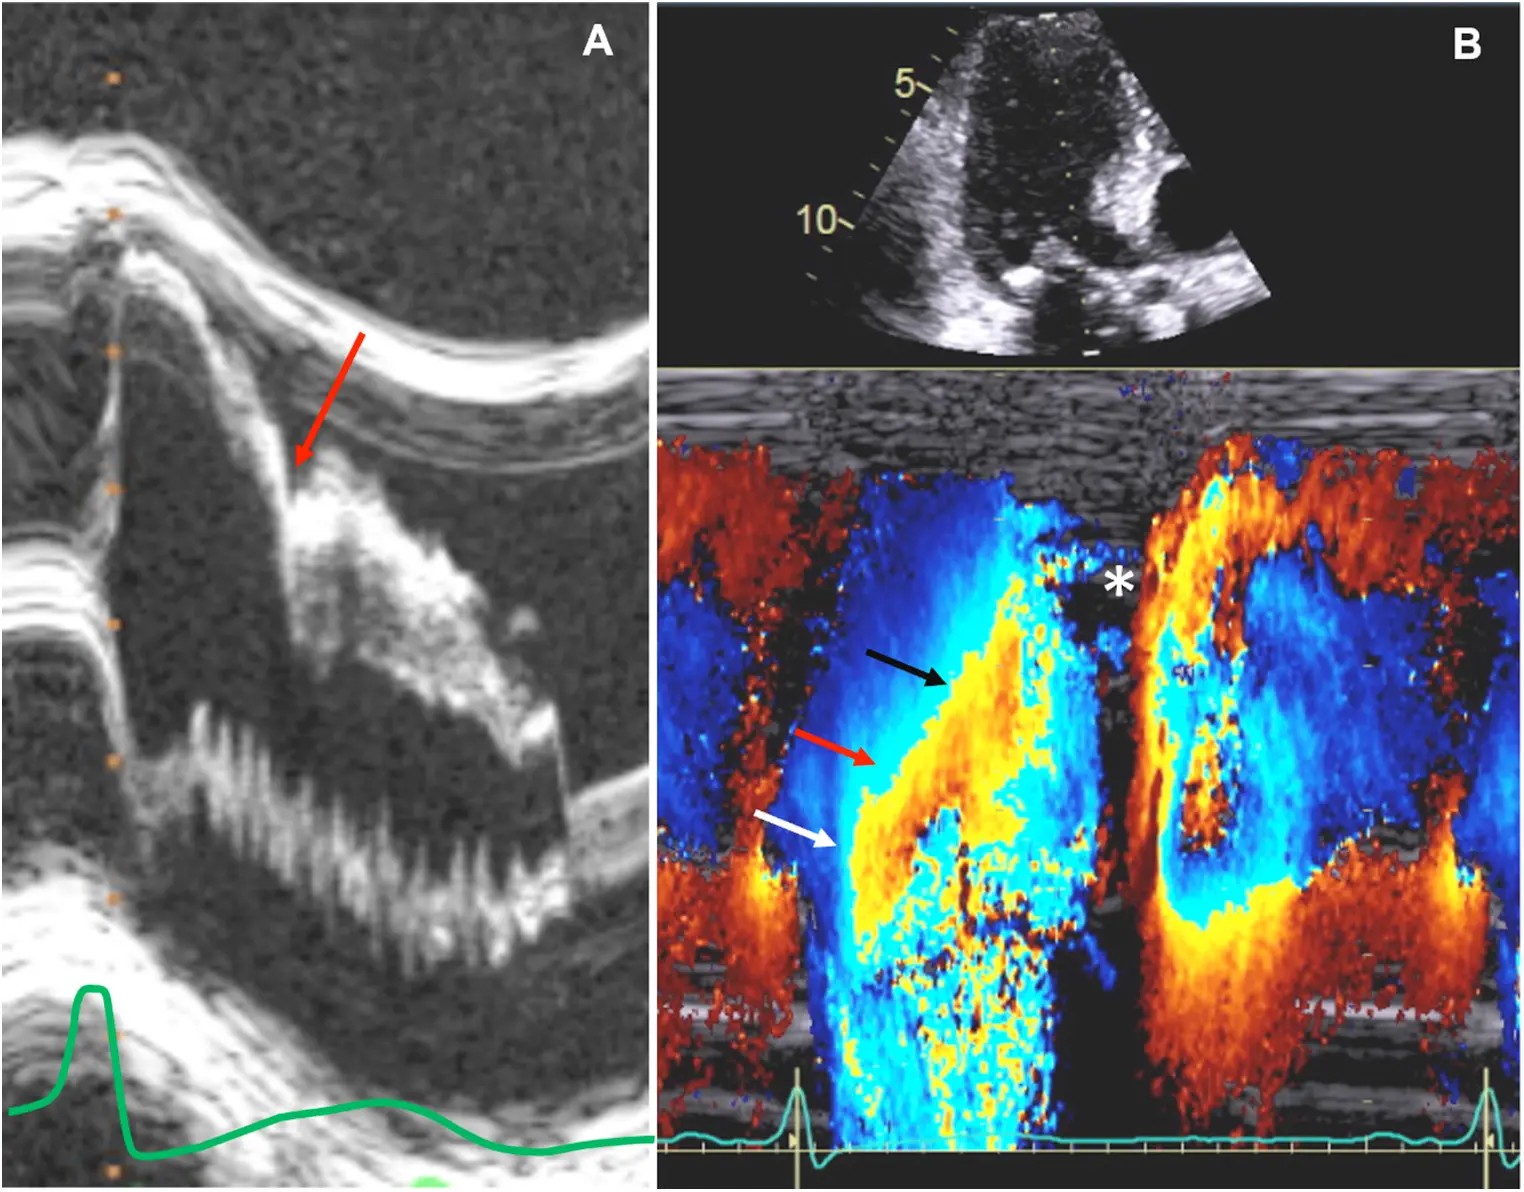

- Color-flow Doppler shows turbulence at mid-ventricular level

- CWD typically shows a narrow, late-peaking systolic velocity (“ice pick” appearance)

M-mode

- Temporal resolution of M-mode → the duration of SAM where it is in contact with the septum correlates w/ severity of LVOT obstruction

Notice the turbulence, which suggests LVOTO